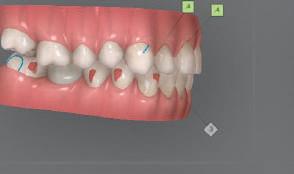

следните казуси: недобра оклу зия в дисталните зони по вре ме на дистализирането на гор ната челюст и накланяне на зъб #21 (фиг. 7). Последното се дължи на липсата на компози тен атачмънт на този зъб, каквото не бе зададено в пър Фиг. 4 Телерентгенография и цефалометричен анализ преди началото на лечението. Фиг. 5a–e Одобреният първоначален лечебен план. Фиг. 6a–h Снимки по време на лечението, показващи нуждата от внасяне на някои корекции. Фиг. 4 Фиг. 5a Фиг. 5d Фиг. 6a Фиг. 6d Фиг. 6f Фиг. 6b Фиг. 6e Фиг. 6g Фиг. 6h Фиг. 6c Фиг. 5e Фиг. 5b Фиг. 5c

Dental Tribune Bulgarian Edition / октомври 2022 г.18 воначалния план. Тези пробле ми бяха адресирани чрез допъл нителна поръчка на алайнери с торк контрол и зададено екст рудиране на задните зъби с цел установяване на добри оклузал ни контакти в дисталните об ласти, като бяха предвидени и оптимизирани атачмънти с контрол над корените за корекция на ангулацията на макси ларните резци (фиг. 8). Резултати от лечението Панорамната рентгено графия след ортодонтското лечение показа благоприятна паралелна позиция на съседни те зъби, подходяща за поставя не на имплант в областта на #22, както и конвергенция на ко рените на зъби #44 и 45 (фиг. 9), но преценихме, че няма да от деляме допълнително лечебно време за коригирането ѝ поради факта, че пациентката бе мно го доволна от постигнатия до момента резултат. След при ключване на лечението бяха постигнати отлични взаимо отношения клас I при мола рите и канините, а срединни